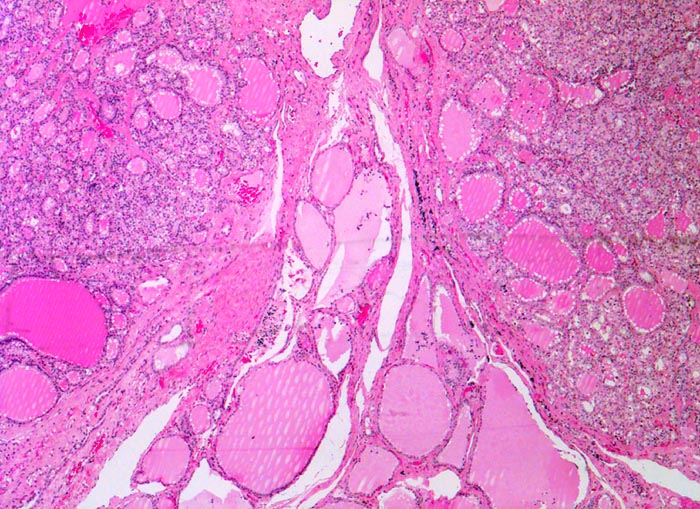

- Anschnitt eines grossen mikrofollikulären Knotens (autonomes Adenom) mit angedeuteter Kapsel und zentraler Einblutung. Oben zwei weitere kleine Satellitenknoten.

- Kompression des angrenzenden Schilddrüsenparenchyms. Dieses besteht aus grossen Follikeln mit kubischem oder abgeflachtem Epithel und reichlich kompaktem dunklem Kolloid in den Follikellumina.

- Zeichen gesteigerter hormoneller Aktivität im Adenom:

- Kleine Drüsenlumina.

- Teils mehrreihiges kubisches bis zylindrisches Epithel.

- Fehlendes oder nur spärliches helles Kolloid mit zahlreichen Resorptionsvakuolen.